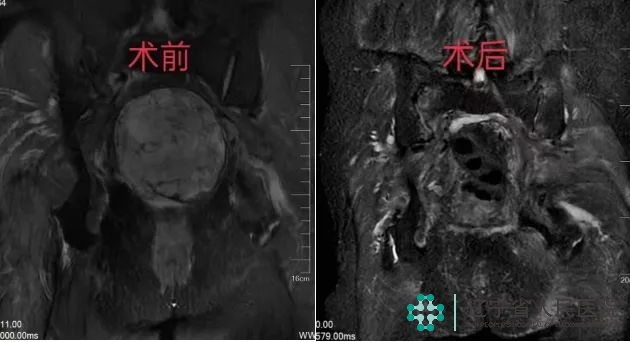

术前、术后MRI对比

团队专家经过了几轮研讨,进行术前会诊,最后制定了经骶1-2截骨、骶骨肿瘤En-bloc全切术(保留一侧骶1-3神经根)的方式为赵阿姨进行手术。

整个手术持续大约4小时,非常顺利,术中有效地控制了出血量,在肿瘤完整切除的同时又保护了患者的大小便功能,术后病理结果确诊肿瘤为脊索瘤。